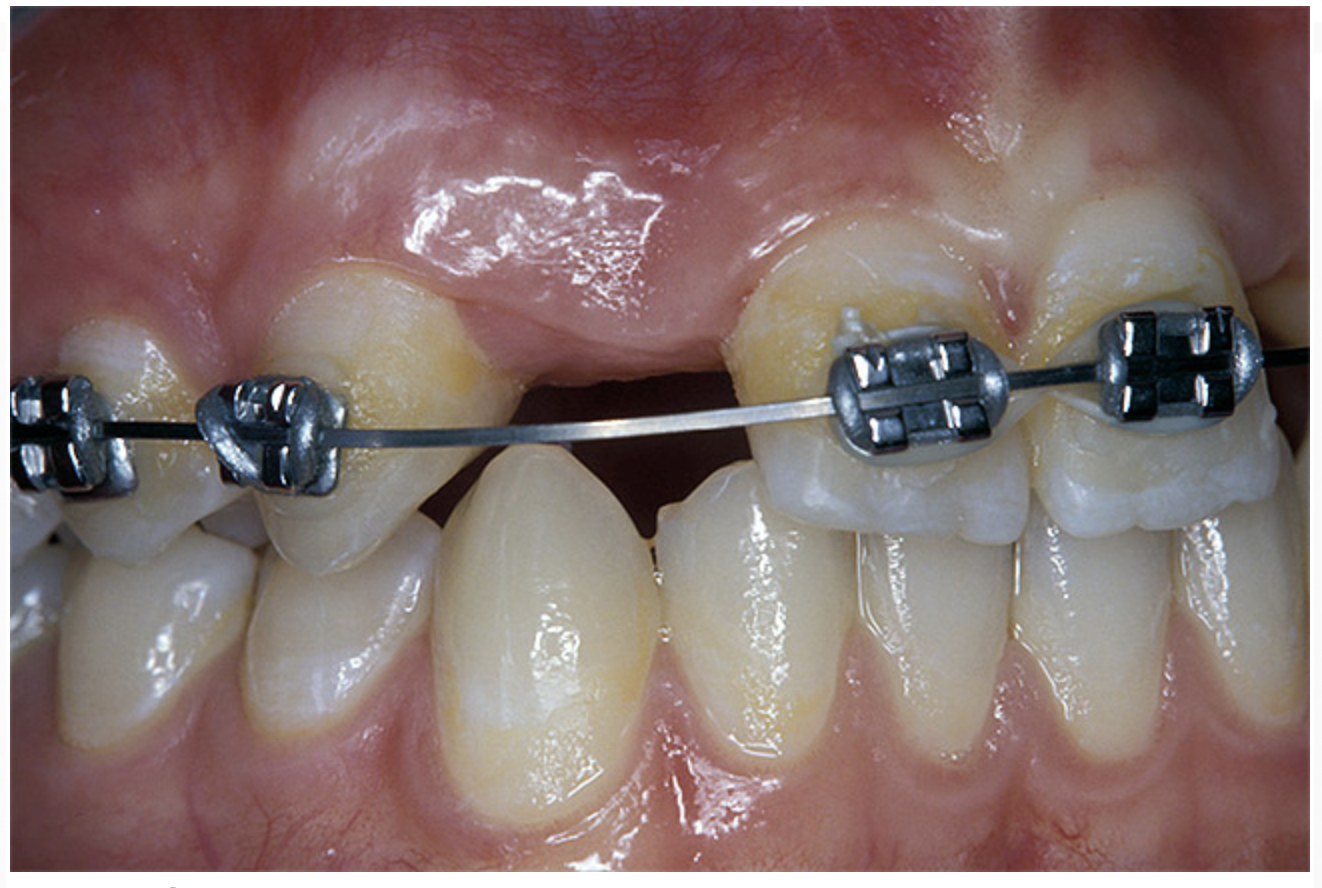

Periapical radiographs were taken to help determine the mesial-distal inclinations of the adjacent tooth roots (Figure 1). The radiographs revealed a serious issue, convergent roots for the right canine and right central, which eliminated that area as a potential implant-receptor site. The space between the left central and canine teeth was minimal, although the roots were relatively parallel. Clinical examination (manual palpation of the root eminences superiorly to the vestibule on the right side) confirmed the root convergence (Figure 2A). The flat, wide zone of the keratinized tissue and lack of interdental papilla was evident for the missing right lateral incisor. There was a marked difference in clinical appearance for the left lateral, which could impact the eventual plan of treatment (Figure 2B). Other significant clinical findings included bilateral facial bone concavities, which existed as a result of the congenitally missing tooth roots. As a diagnostic cue to the underlying bone topography, it is important to follow the demarcation between attached and unattached gingival tissue, and note the crestal width of the available keratinized tissue (Figure 2C).

Figure 2a  Pretreatment buccal views showed (A) root convergence, (B) a difference in clinical appearance of the left lateral, and (C) significant crestal width of keratinized tissue.

Figure 2b  Pretreatment buccal views showed (A) root convergence, (B) a difference in clinical appearance of the left lateral, and (C) significant crestal width of keratinized tissue.

Figure 2c  Pretreatment buccal views showed (A) root convergence, (B) a difference in clinical appearance of the left lateral, and (C) significant crestal width of keratinized tissue.